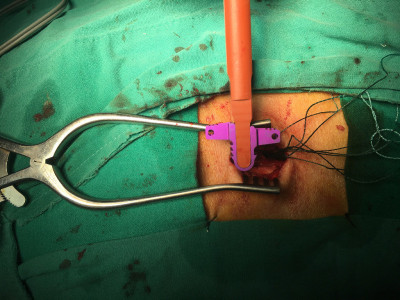

Artroplastía lumbar y prótesis de columna

Envíado por Dr. Hugo Enrique Castro Cordero